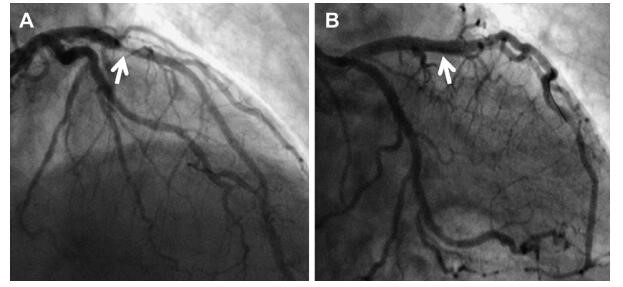

支架植入有两个植入阶段,一是在急性期,心肌梗死刚刚发病的12-24小时以内,我们也叫急诊支架植入,其效果最好,植入越早,其坏死心肌也就越少,也是目前最为前沿的救治方式。另一种支架植入是在心梗恢复期,在心梗后7-10天以后,进行择期进行的支架植入,这样的方式,已经没有急诊支架植入的效果明显了。